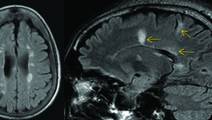

Radiologic Differential Diagnosis of Multiple Sclerosis

Practical Neurology: Focus on Multiple SclerosisRadiologic Differential Diagnosis of Multiple Sclerosis

Radiologic Biomarkers in Multiple Sclerosis: Improving Detection and Diagnosis

Practical Neurology: Focus on Multiple SclerosisRadiologic Biomarkers in Multiple Sclerosis: Improving Detection and Diagnosis